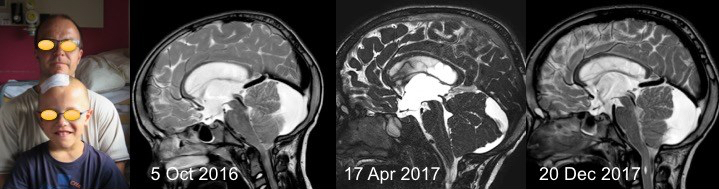

les problèmes hydrauliques de l’achondroplasie

ils sont classiquement dus à une compression veineuse au niveau des foramens jugulaires, rendue responsable de la macrocrânie habituelle chez ces patients.

Le PC est « normalement » augmenté dans l’achondroplasie. il existe donc des courbes de PC spécifiques des achondroplastes, garçons et filles.

cette expansion des espaces liquidiens peut favoriser la constitution d’une collection sous-durale post-traumatique.

les troubles hydrauliques peuvent intriqués avec un engagement tonsillaire, mais ils peuvent en être aussi bien la cause que la conséquence, ce qui laisse donc une place au traitement endoscopique.

il faut le plus possible éviter de mettre en place une valve, qui comporte un risque important de complications, du fait notamment de perturbations de la croissance crânienne.